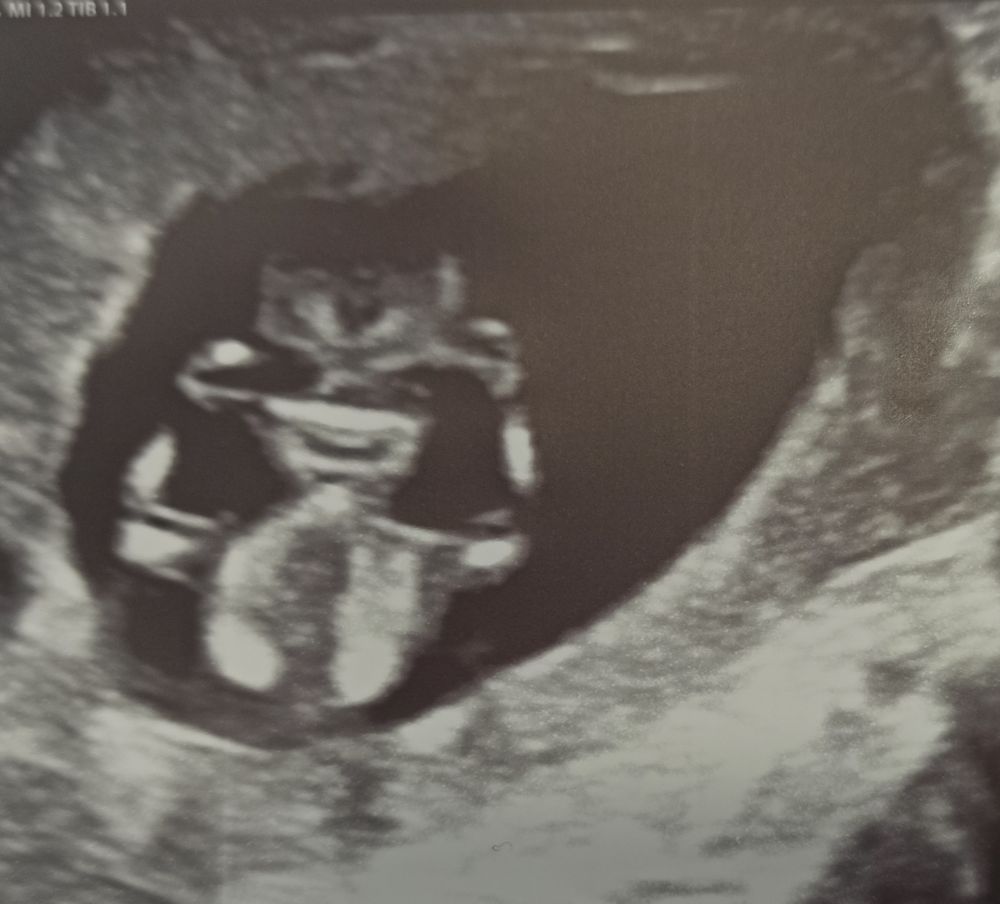

УЗИ 72 дпо (12+1) ❤🤞🤞🤞

Какой милый малыш! 😍 Благополучных вам неделек и крепкого здоровья! ❤🙏

Все у Вас прекрасно☺️ Малыш хорошенький❤️ Мы с Вами +- по пдр близко☺️